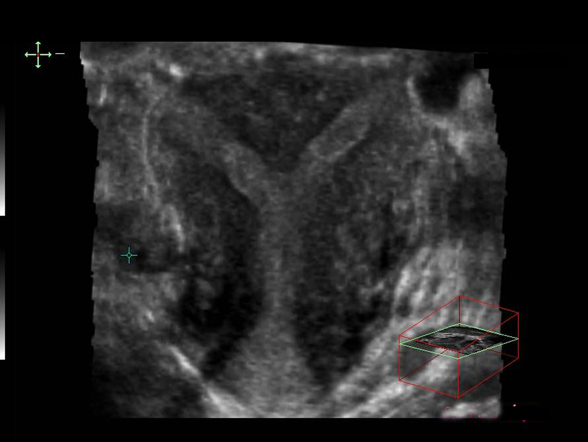

Utérus cloisonné (écho 3D)